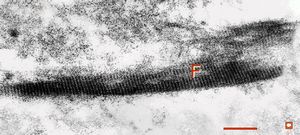

M,41y. | ribosome-lamella complex in tricholeukocyte -hairy cell leukemia, spleen

M,41y. | ribosome-lamella complex in tricholeukocyte -hairy cell leukemia, spleen

M,41y. | ribosome-lamella complex in tricholeukocyte -hairy cell leukemia, spleen